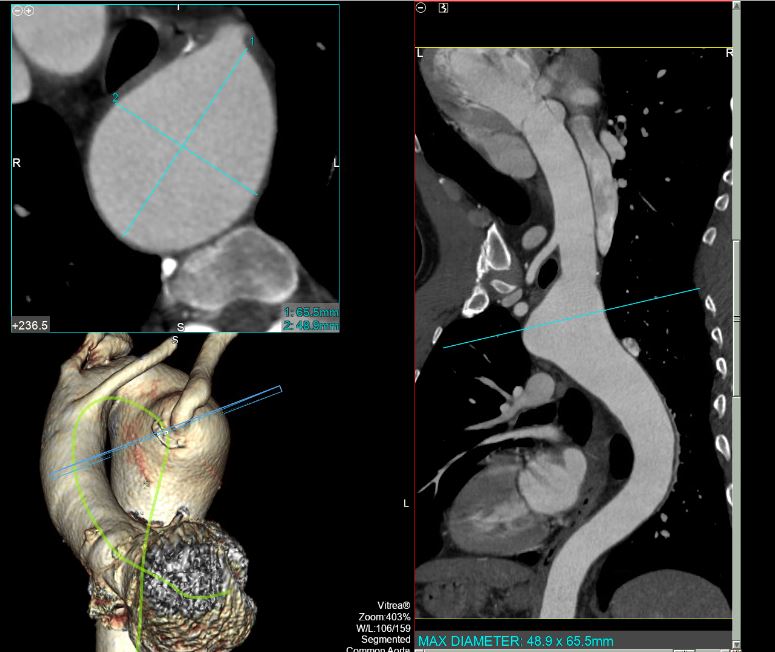

Case Presentation: 56-year-old male patient with PMHx of HTN, HLD, pulmonary embolism and cigarette smoking presented to the emergency department with recurrent chest pain. He described his chest pain as substernal, non-radiating, He was evaluated multiple times for ischemic etiologies of his pain and, associated with SOB but no nausea or vomiting. work up was negative including pharmacological stress test. The patient had multiple similar previous presentations without a clear cause of his chest pain. The patient denies any shortness of breath or dysphagia. During this admission, the patient underwent computed tomography angiogram (CTA) of the chest to rule out aortic dissection, which revealed right sided aortic arch with aberrant origin of the left subclavian artery and an aneurysmal dilatation of the arch measuring 5.5 x 5.1 cm involving the origin of the aberrant left subclavian artery representing Kommerell diverticula. Previous records from outside hospital reviewed and revealed similar findings. It was planned to manage the patient conservatively giving location of the aneurysm and stability in size. The patient underwent a follow up CTA after 6 months with stability in the size of aneurysm.